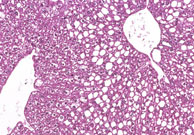

Fatty change, mild. The circular clear spaces represent areas previously occupied by fat in this mouse on a choline deficient diet. The fat is dissolved out by xylene during processing of the tissue.